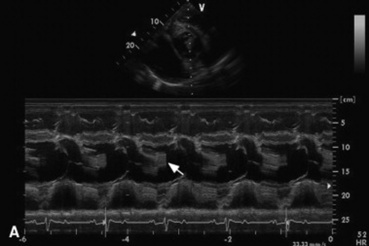

Echocardiography is the diagnostic technique of choice for identifying a VSD. With two-dimensional echocardiography the VSD can be imaged directly (Fig. 30-5) and the shunt size, location, and direction demonstrated with pulsed wave Doppler, continuous wave Doppler, color flow echocardiography, or the injection of microbubbles. Careful scanning of the interventricular septum should be performed with two-dimensional echocardiography to directly image the VSD and measure its maximal diameter in two mutually perpendicular planes.31,32 The typical membranous VSD (≤2.5 cm in both planes) is missed if the long-axis view of the left ventricular outflow tract is not examined. The membranous VSD is located underneath the septal leaflet of the tricuspid valve and the right or noncoronary leaflet of the aortic valve. If a membranous defect is not found, the entire septum should be carefully scanned in all imaging planes to detect the VSD. The subpulmonic location, more common in calves, is easy to miss. This defect is usually best imaged in the short-axis view, scanning the interventricular septum between the left and right ventricular outflow tracts. With a left-to-right shunt a high-velocity turbulent jet is depicted from the right parasternal window, originating in the left ventricle, traversing through the hole in the interventricular septum into the right ventricle with color flow Doppler echocardiography (blood flow toward the transducer), whereas a negative contrast jet is imaged in the right ventricle with a right-sided injection of microbubbles.31,32 A left ventricular injection of microbubbles is necessary to visualize echo-laden blood in the right ventricle with a typical VSD. M-mode echocardiography may show septal discontinuity when traversing the ventricular septum from the apex of the heart to the aortic root (septal dropout). Moderate to large VSDs show left atrial and left ventricular enlargement, right ventricular enlargement, and pulmonary artery dilation. The left atrial—to—aortic root ratio is increased. Aortic valve prolapse and aortic regurgitation may also be detected because of loss of support of the aortic root from the VSD. Myocardial dysfunction and subsequent CHF may occur with a large VSD. Continuous wave Doppler echocardiography can be used to noninvasively assess the hemodynamic significance of the shunt (see Fig. 30-5, B). A peak shunt flow velocity of greater than or equal to 4 m/sec indicates a restrictive VSD with normal or near normal right ventricular pressures. Nuclear angiocardiography can also be used to demonstrate simultaneous opacification of the left and right ventricles. The radiographic presence of cardiomegaly and increased vascularization of the lungs provides only nonspecific evidence of VSD. If polycythemia is found, a complicated VSD should be suspected.

image

Fig. 30-5 Two-dimensional echocardiographic image (A) and continuous wave Doppler spectral tracing (B) of a ventricular septal defect (arrow) in a weanling colt. The ventricular septal defect (VSD) is located just underneath the septal leaflet of the tricuspid valve and right coronary cusp of the aortic valve. The VSD is best imaged in this left ventricular outflow tract view. There is significant left ventricular enlargement in this colt. The right atrium (RA), right ventricle (RV), left ventricle (LV), left atrium (LA), aortic root (AR), and pulmonary artery (PA) are all visible in this view. The spectral tracing shows a peak shunt velocity of slightly under 4 m/sec in systole, with some turbulent flow (spectral broadening) also detected in diastole with a peak flow velocity of approximately 1.3 m/sec.